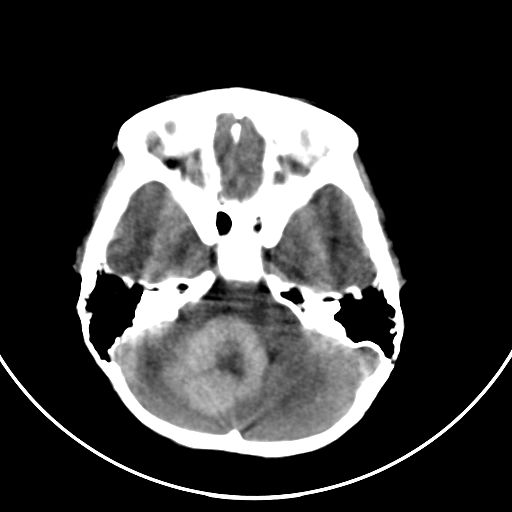

以下是引用zjzjr在2008-7-27 9:56:00的发言:[br]考虑髓母细胞瘤伴梗阻性脑积水.建议增强或mri

以下是引用子十在2008-7-27 9:53:00的发言:[br]考虑髓母细胞瘤